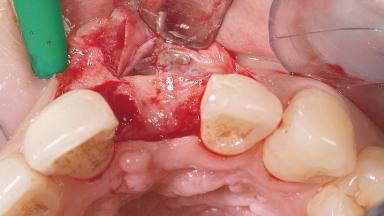

A 30-year-old female patient had lost tooth 21 and was referred to our clinic for consultation and treatment. Due to advanced apical infection, tooth 21 had been extracted two months earlier at another clinic and an acrylic-resin tooth had been bonded to the adjacent teeth. The patient desired implant treatment to avoid any damage to the adjacent natural teeth. While the patient had no history of any systemic disorder, she was a heavy smoker and exhibited medium to advanced periodontitis in the entire jaw. After the initial treatment to achieve a pocket probing depth of less than 4 mm and no bleeding on probing, a decrease in the height of the papillae mesial and distal to the extraction site and overall gingival recession were observed.

Bone Augmentation Horizontal|Staged

Augmentation Materials Autogenous chips|Membrane

Soft Tissue Grafting Simultaneous

Soft Tissue Anatomy Intact Defective

Bone Volume Horizontally and vertically sufficient Horizontally deficient Deficient vertically or deficient vertically AND horizontally

Bone Volume Deficient horizontally, requiring prior grafting